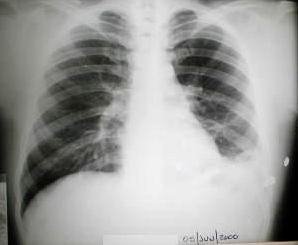

• Radiología del Tórax

Rx. tórax (hace 6 meses), posterior al egreso de su antecedente traumatico.

Rx. Tórax al momento de su Ingreso. motivo de su referencia a nuestro hospital.